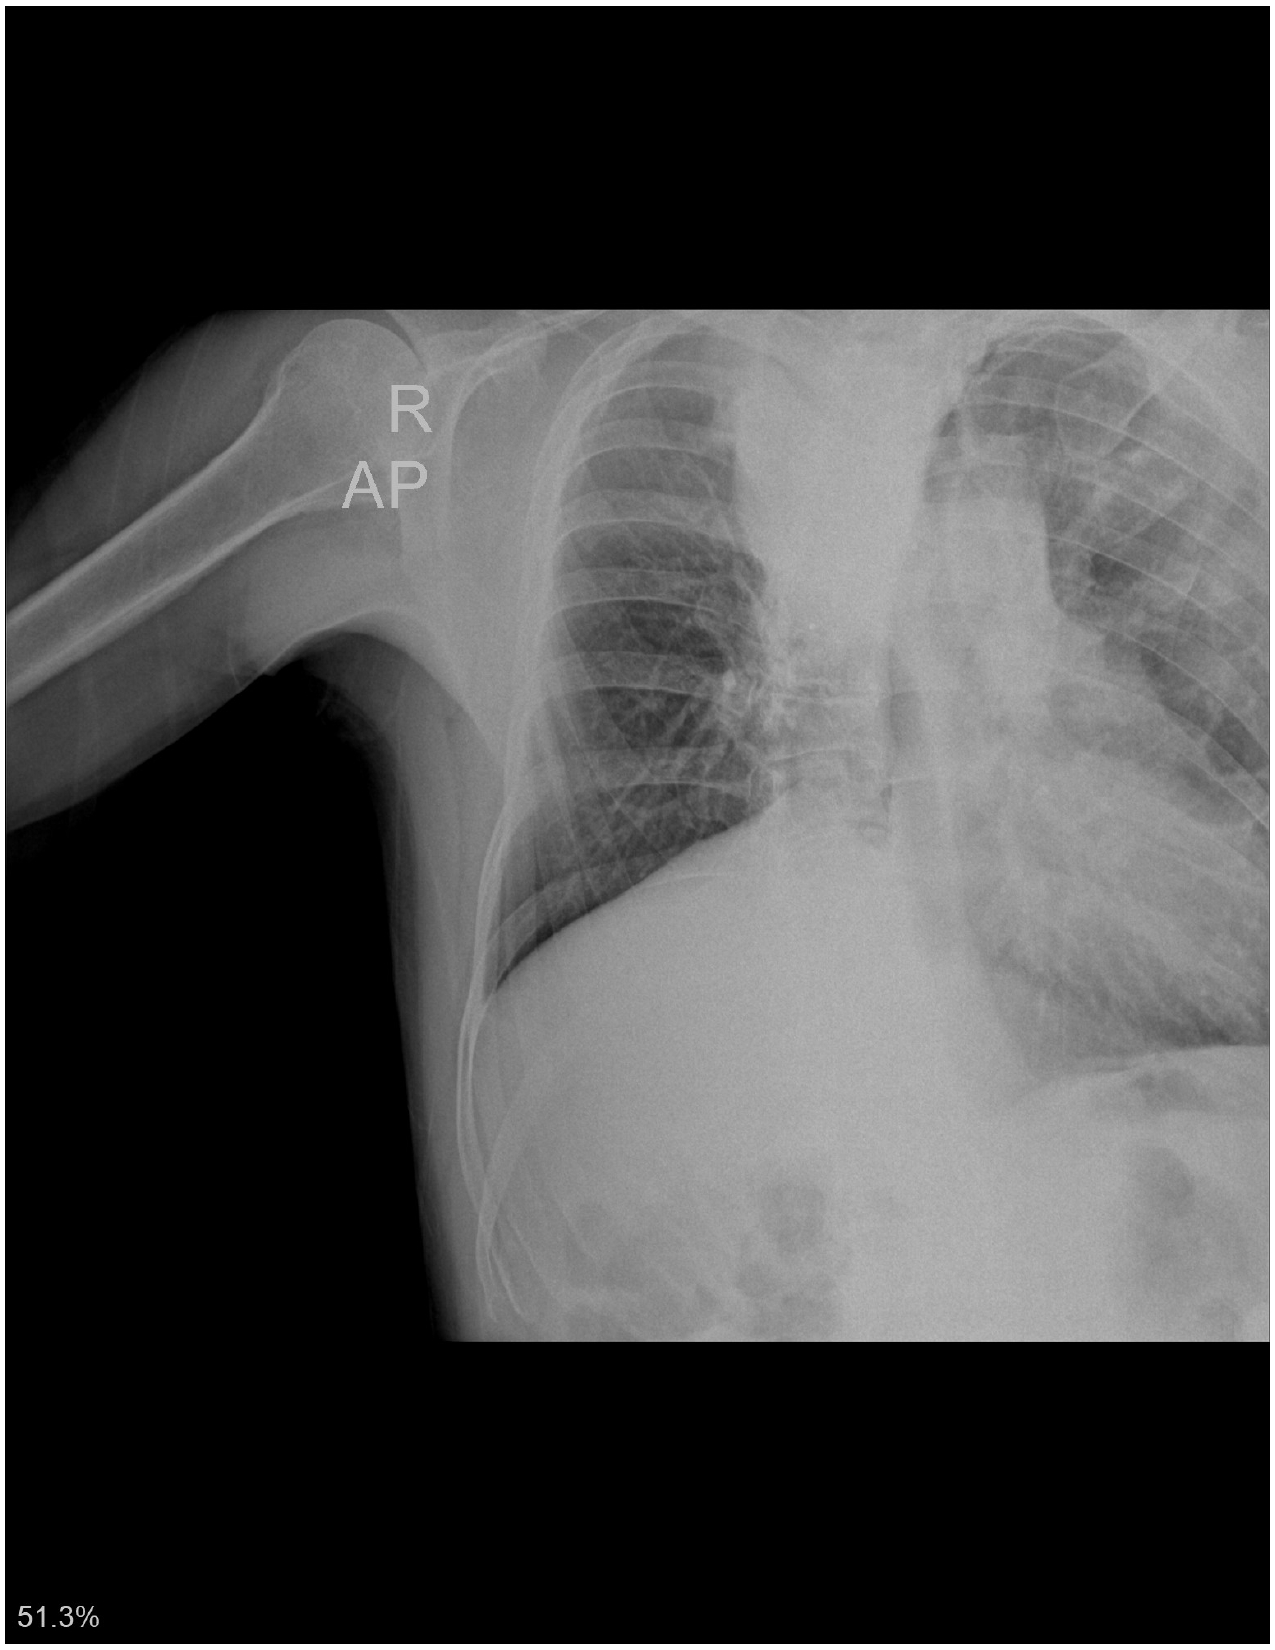

- გულმკერდის CXR სტენტირების დღეს.